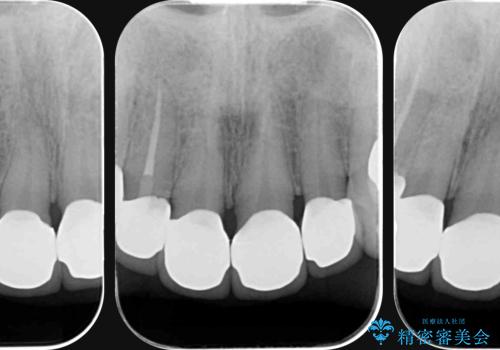

- 放置した虫歯の歯がボロボロになってしまい治療を希望され来院されました。

残根状態の歯、神経まで虫歯が達し失活した歯、歯肉縁下まで及んだ虫歯が多数認められます。

まず虫歯を拡大鏡、マイクロスコープ下で丁寧に取り除き歯肉縁下の虫歯を歯周外科により解決したのち、ジルコニアクラウン製作を行っていきます。